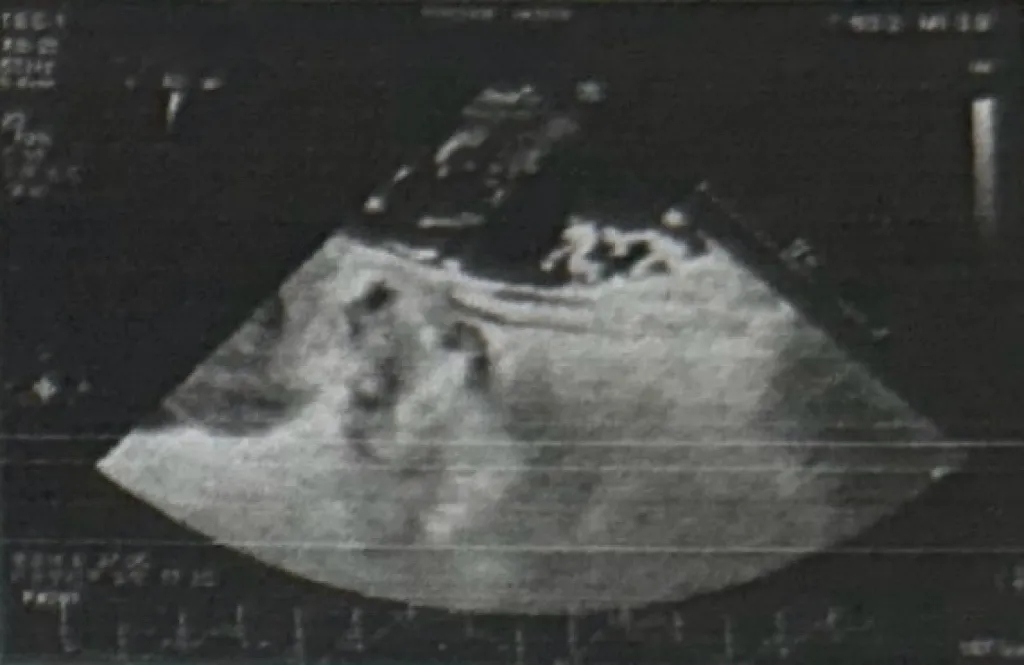

外院食道超声下右心声学造影呈阳性

外院经食道测量PFO长度17mm,宽度2.5mm